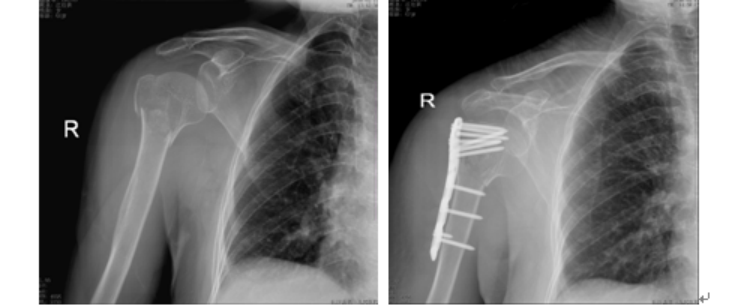

丙烯酸骨水泥在骨科手术中发挥着重要作用,其中聚甲基丙烯酸甲酯(PMMA)已从最初的眼科和牙科领域,扩展至骨科领域,并广泛地应用于假体内植物的固定、肿瘤和椎体骨折的治疗。骨质疏松性股骨近端骨折使用骨水泥强化的内固定系统可以减少约50%的失败率,主要适应症是不稳定型脆性骨折[24]。对骨科医生来说,骨量减少的肱骨近端骨折患者的治疗充满挑战。尽管内植物的设计不断改良,但螺钉或螺旋刀片在肱骨近端松质骨内的把持力仍然不足,而这也是内固定失败最主要的原因之一。骨水泥强化技术即将骨水泥注入肱骨头内,填补了内植物与肱骨头之间的空隙,从而增强内植物的把持力[25]。近年来,采用中空的螺钉结合角度稳定钢板系统,骨水泥可以通过中空的螺钉注入,达到骨水泥强化的效果[25]。骨质疏松性胫骨平台骨折与髋部骨折、肱骨近端骨折都不同,它是由于垂直应力直接作用于骨量减少的软骨下骨组织,造成关节面的凹陷和/或劈裂;其经典手术方式是通过植入自体或异体松质骨,支撑重建关节面[26]。但是,自体或异体松质骨在骨折愈合阶段,无法提供足够的力学支撑,造成关节面塌陷,利用骨水泥强化技术可能改善上述情况。